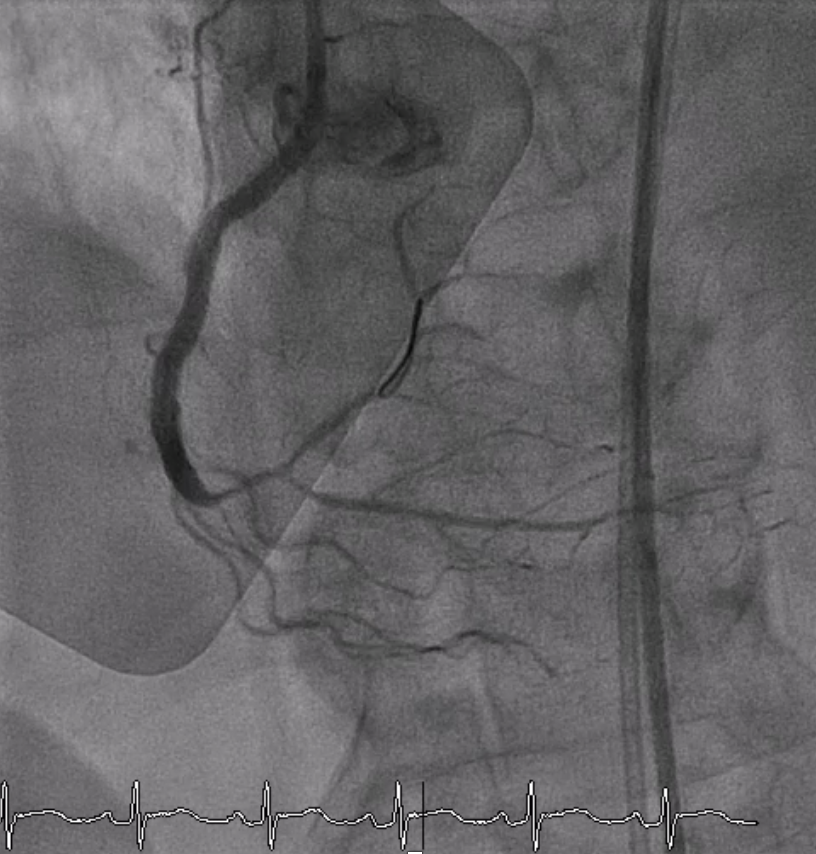

A 6 Fr JR 4.0 guiding catheter was engaged via femoral approach and JL 4 catheter was used for dual injection. We planned to perform PCI at proximal RCA CTO with antegrade wire escalation technique first. We successful wired to PL branch of RCA using microcatheter with Gaia Next 2 guidewire (Failed using Fielder XT). The microcatheter could not cross lesion. Try using CTO balloon 0.75/8 mm and 1.0/6 mm to pre-dilatation but still uncrossable. So we put the microcatheter farthest and successful bare wiring the RotaWire Floppy to PL. Rotational atherectomy was done with Burr 1.25 mm at 172,000 - 146,000 rpm total 4 runs. IVUS was pulled back from PL-RCA showed intra-plaque wiring, calcified nodules with cracked calcific plaques and reverberation. We prepared the lesion proximal to mid RCA lesion with non-compliant 2.5/15 mm balloon at 20 atm and scoring 3.0/13 mm balloon at 18-20 atm. A 3.0/38 mm stent could not be delivered the lesion. We used the guide extension catheter with balloon-assisted tracking techinque for delivery. The stent was successfully deployed to mid RCA. The 3.5/28 mm stent was deployed to proximal to mid RCA and 3.5/18 mm stent was deployed at ostial RCA. Post-dilatation with non-compliant 3.0/15 and 3.5/18 mm at 16 atm. Final angiogram showed good coronary blood flow and IVUS demonstrated well stent expansion, no malapposition and no stent edge dissection.